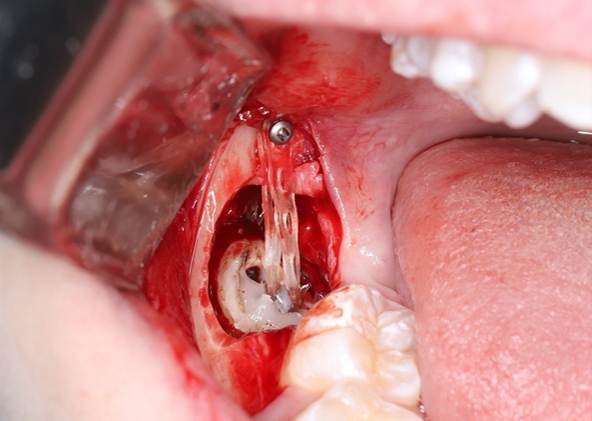

4. Установка мини-винта

Ставим винт в кость рядом с зубом. Это опора для вытягивания зуба.

Выглядит так

Размер винта подбирается по КТ-снимку. Мы используем корейские винты Bio-Ray. Для установки используются специальные отвёртки.

5. Крепление тяги

Ставим на зуб ортодонтическую кнопку с помощью адгезивной системы и пломбы. К ней крепим эластичную цепочку, которая соединяется с мини-винтом. Зашиваем надрез на десне.

Здесь наглядно видно